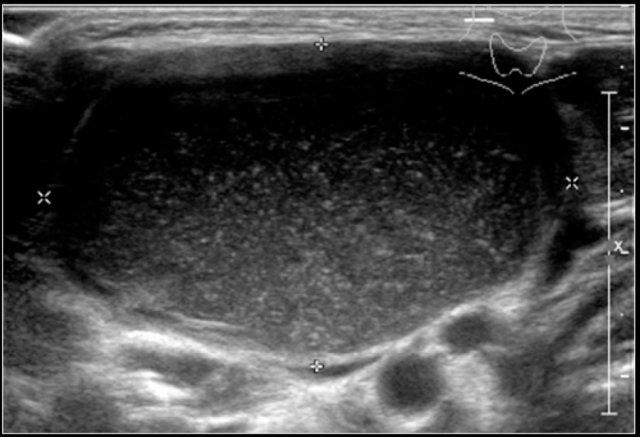

Đây là hình ảnh siêu âm của một u mạch bạch huyết điển hình.

MRI được thực hiện vì sự lan rộng của tổn thương chưa được xác định rõ ràng.